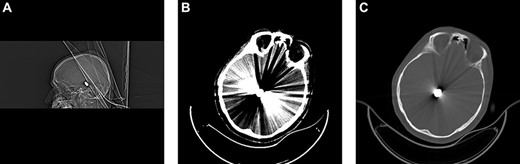

Emergent unenhanced head computed tomography (CT) was performed, which revealed a bone defect in the left parietal region and a metallic object in the posterosuperior side of the mesencephalon. The bullet had entered through the left parietal lobe. Associated hemorrhage was observed along its trajectory in addition to subarachnoid hemorrhage and minimal brain edema. However, the metal artifacts obscured the damage (Fig. 1). The entry wound was debrided and sutured. The patient was admitted to the neurosurgical intensive care unit and was conservatively treated with prophylactic antibiotics, antiedema medications, sedatives (pentobarbital) and antiepileptic drugs.

Brain CT upon admission revealed the bullet fragment located deep to the convexity of the skull. (A) Sagittal bone window. (B) Brain. (C) Axial bone window.